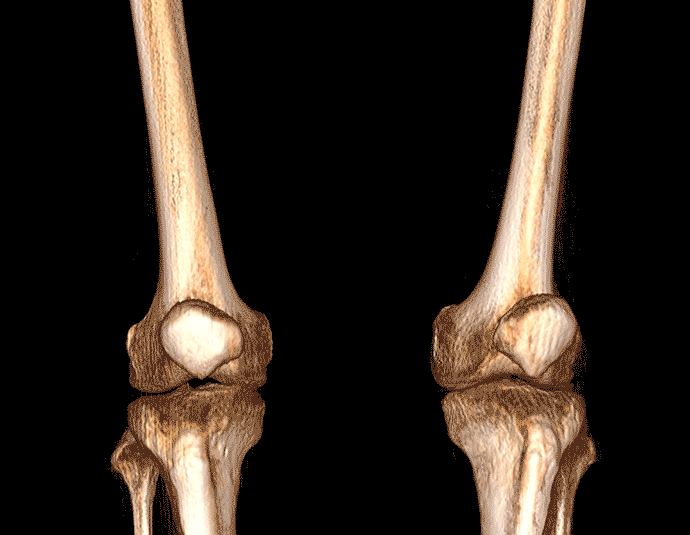

膝关节

精准诊断

手术方案规划

术后随访

VR体绘制重建